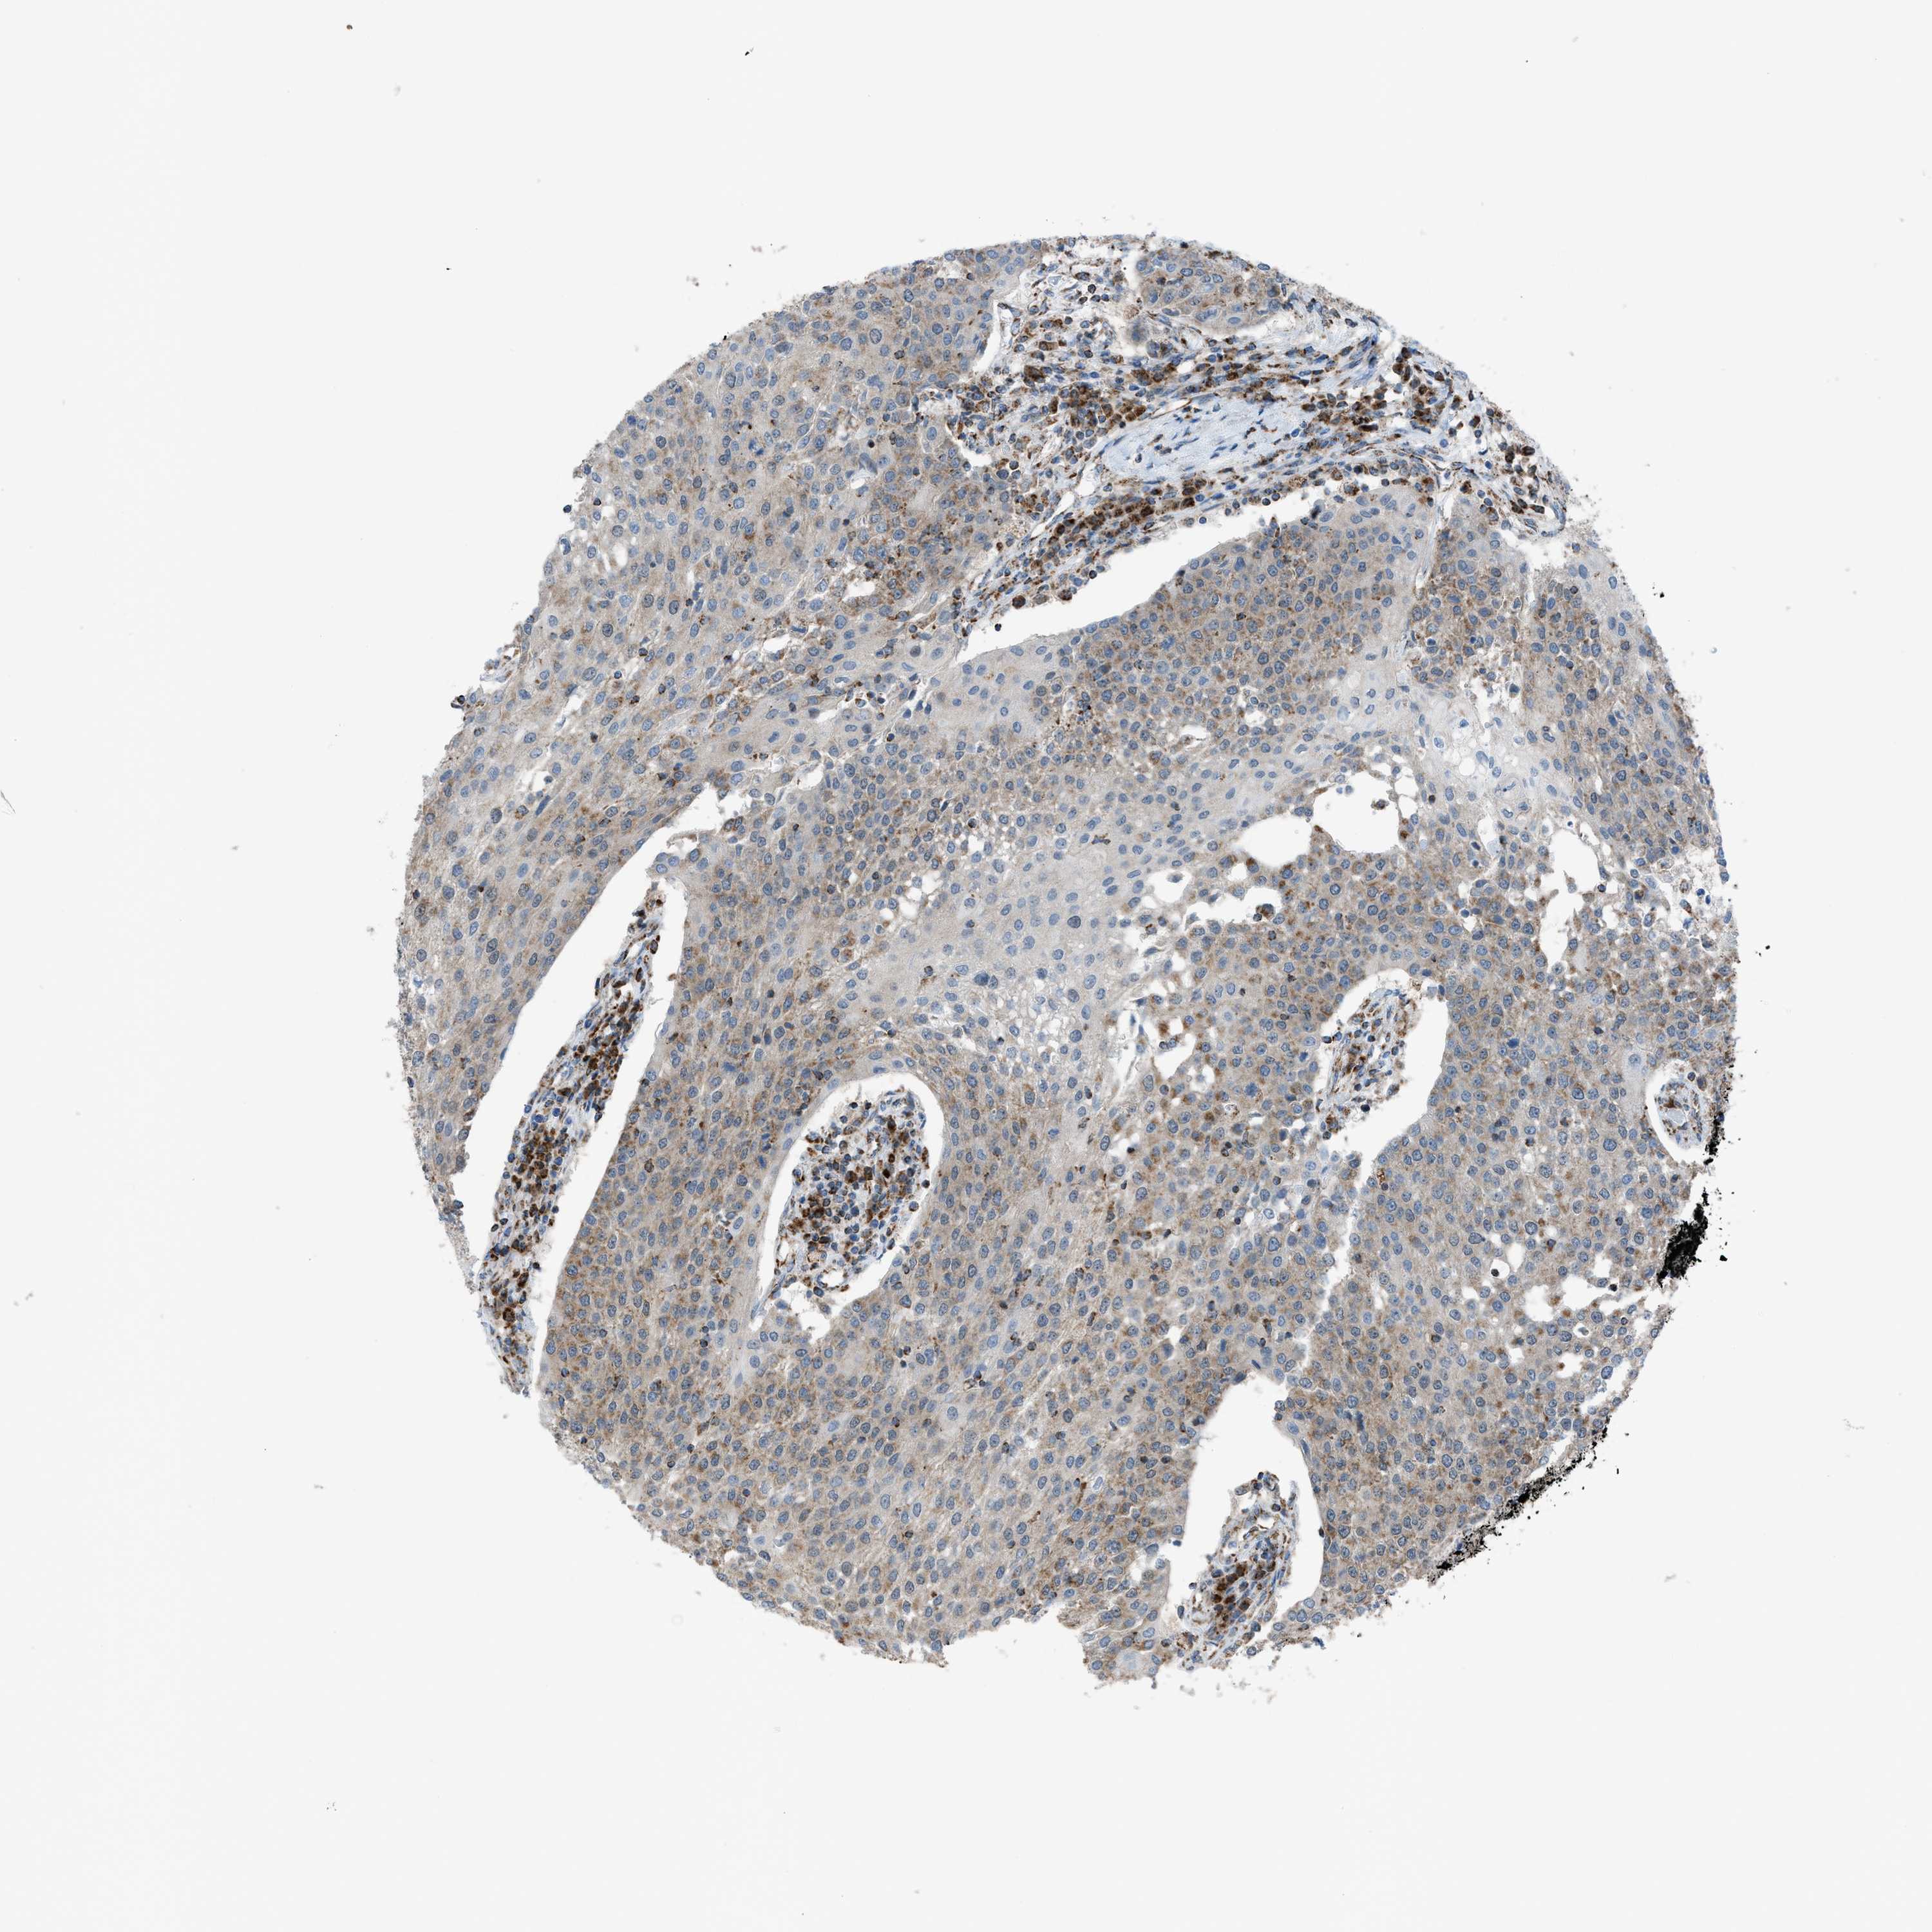

UROTHELIAL CANCER - Protein expressioni

A mouse-over function shows sample information and annotation data. Click on an image to view it in a full screen mode. Samples can be filtered based on level of antibody staining by selecting one or several of the following categories: high, medium, low and not detected. The assay and annotation is described here.

Note that samples used for immunohistochemistry by the Human Protein Atlas do not correspond to samples in the TCGA dataset.

Antibody stainingi

Antibody staining in the annotated cell types in the current human tissue is reported as not detected, low, medium, or high, based on conventional immunohistochemistry profiling in selected tissues. This score is based on the combination of the staining intensity and fraction of stained cells.

Each image is clickable and will lead to virtual microscopy that enables deeper exploration of all samples and also displays staining intensity scores, fraction scores and subcellular localization as well as patient and tissue information for each sample.

Antibody HPA015746

Staining

High

Medium

Low

Not detected

Intensity

Strong

Moderate

Weak

Negative

Quantity

>75%

75%-25%

<25%

None

Location

Nuclear

Cytoplasmic/membranous

Cytoplasmic/membranous,nuclear

Urothelial carcinoma, Low grade

Urothelial carcinoma, High grade